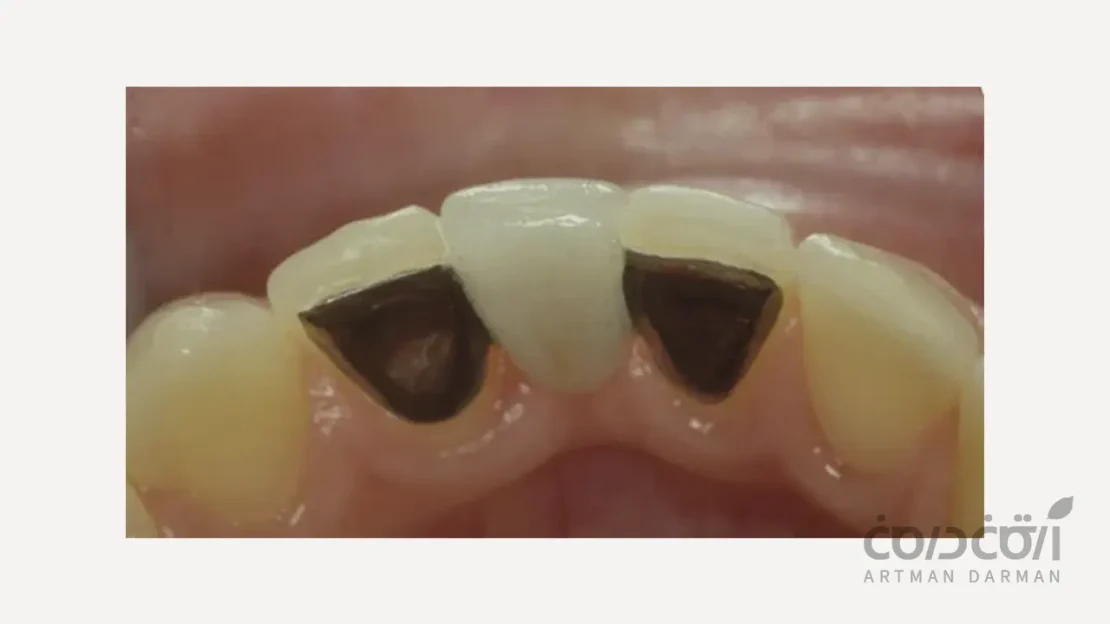

بریج متصل شونده با رزین (Resin-Bonded Bridge یا Maryland Bridge)

یک دندان مصنوعی با دو باله نازک که به پشت دندان های سالم مجاور چسباندهمیشود. مزیت اصلی آن، عدم نیاز به تراش دندان های سالمِ کناری است. که این رویکرد کاملاً با اصول دندانپزشکی محافظه کارانه همخوانی دارد.